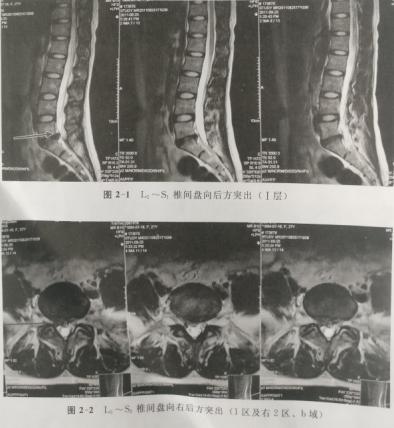

病例1.李某,男,37岁,于2011年5月7日确诊为腰椎间盘突出症,磁共振显示L5--S1椎间盘向左后方脱出并游离于L5椎体后方。患者因工作不允许离开岗位且无明显神经损害体征,行保守治疗并随访,症状逐渐减轻。2012年4月20日复查磁共振突出髓核明显缩小,几乎消失。

病例2.刘某,女,28岁,于2011年8月25日确诊为腰椎间盘突出症,磁共振显示L5--S1椎间盘向右后方突出,达1区级右2区、B域(椎管矢状径的1/2),硬膜囊明显受压,右侧S1神经根受压。因无明显根性体征,行保守治疗并随访,体征完全消失。8个月后复查磁共振突出髓核基本消失消失。

下面将某疼痛学杂志的报道及图片展示如下;